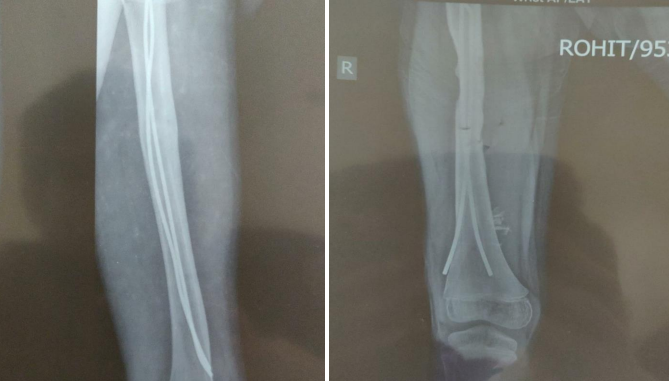

A 10-year-old male patient fell from a height and sustained a direct damage to the shaft of his femur, for which he underwent elastic nail fixation a year ago. He now complains of thigh pain, trouble walking, and knee stiffness for the past six months. On examination, the patient was critically stable, with no head, chest, or abdominal damage, and a normal hip and spine assessment. On local examination, there was swelling with a discharging sinus in the mid-thigh over the anterolateral aspect of 11x4.1 centimetres (superior to inferior and anterior to posterior), with two linear scar marks healed with primary intention over the distal thigh in the medial and lateral aspects, a temperature raised locally, and tendered swelling. Hip joint movements were within normal limits, and knee extension was normal.

All routine investigations were ordered, including an X-ray of the thigh with knee AP and lateral views and an ultrasound for local swelling. On ultrasound, there was a swelling of 11x4.1 centimetres (superior to inferior and anterior to posterior) in the anterolateral part of the mid-thigh, connecting with a sinus measuring 4mm in diameter and not engaging any joint structure.

As a result of the femur shaft fracture, there was no involvement of the knee joint even after elastic nail fixation, no extension of the elastic nail distally, no scar mark over the knee, but on pre-operative x-ray, the medial side elastic nail was not medially but anteriorly. Quadriceps muscles are located anteriorly and are more prone to adhesion and contracture as a result of injury and inflammation.  Because to long-term irritation of the vastus intermedialis muscle near the distal end of the medial side elastic nail, adhesion and contractures form, resulting in knee stiffness.

Figure 1

Figure 2